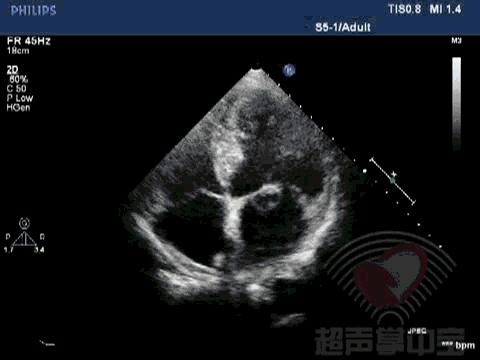

经典病例▏二尖瓣囊肿中竟然全是血液? 图1:心尖四腔心切面显示二尖瓣前叶增厚,前叶左房面可见一囊袋状物附着,大小2.01×2.17cm,囊壁完整,其内透声良好

经典病例▏二尖瓣囊肿中竟然全是血液? 动态图2:四腔心切面显示该囊状物质软,有形变,二尖瓣开放正常